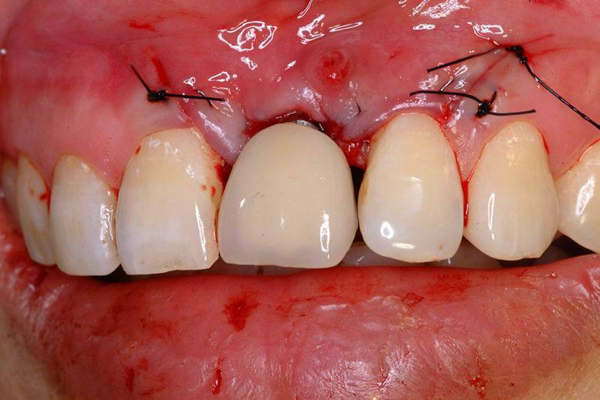

牙周炎圖片

牙周袋 (47)